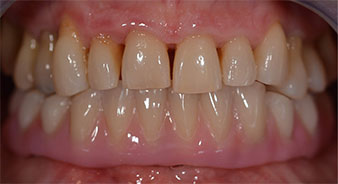

Nach der Zeit, die für die Osseointegration benötigt wird, kann die endgültige Abformung der Implantate erfolgen und entsprechend die endgültige Arbeit angefertigt werden (Abb. 19 und 20). Hier können Behandler und Patient gemeinsam entscheiden, ob diese eine Keramik- oder Kunststoffverblendung, ein Zirkon- oder Metallgerüst bekommen soll. Im vorliegenden Fall hat sich das Team um Dr. Pascu, aufgrund der unklaren Prognose der Oberkieferbezahnung und des elongierten Zahnes 24, für eine Kunststoffverblendung entschieden. Diese ist im Allgemeinen wesentlich einfacher umzustellen und der neuen Situation im Oberkiefer anzupassen.

Osseointegration

Abb. 19

Implantate

Abb. 20